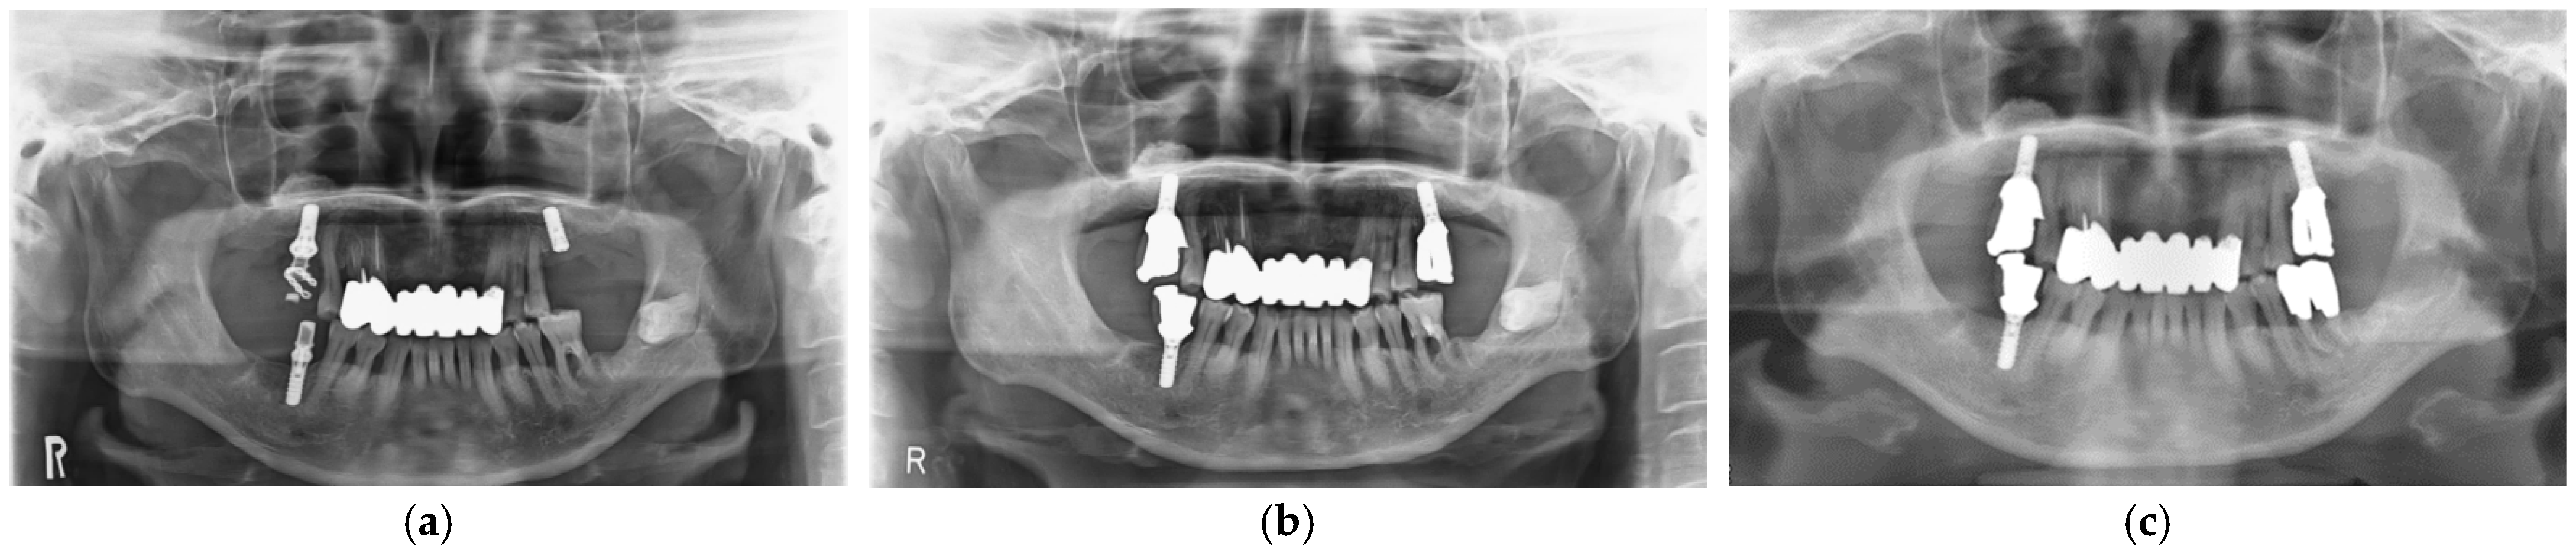

After implant placement, all implant-related surgeries (second operations: connection of healing abutments) and prosthetic procedures were completed successfully. Functional loading with definitive prostheses was possible in all cases. All implants in 12 patients have functioned for 3 years uneventfully. Unfortunately, definitive prosthesis in one patient did not achieve 3-year function, although the implant was loaded for more than 3 years with a provisional restoration. Implant survival rate was 100%. Implant success rate after 3-year functional loading was assessed with clinical findings and panoramic radiographic images based on the success criteria (Figure 5). All implants were stable and showed no mobility. No patients complained of pain or peri-implant soft tissue inflammation. In addition, panoramic radiography analyses showed no continuous radiolucency in the peri-implant bone. These findings revealed that implant success rate was also 100%.

Figure 5.

Panoramic radiographic images. SFE and implant at maxillary left molar site. (a) At implant placement; (b) At the delivery of final restoration; (c) At 3-year follow-up.